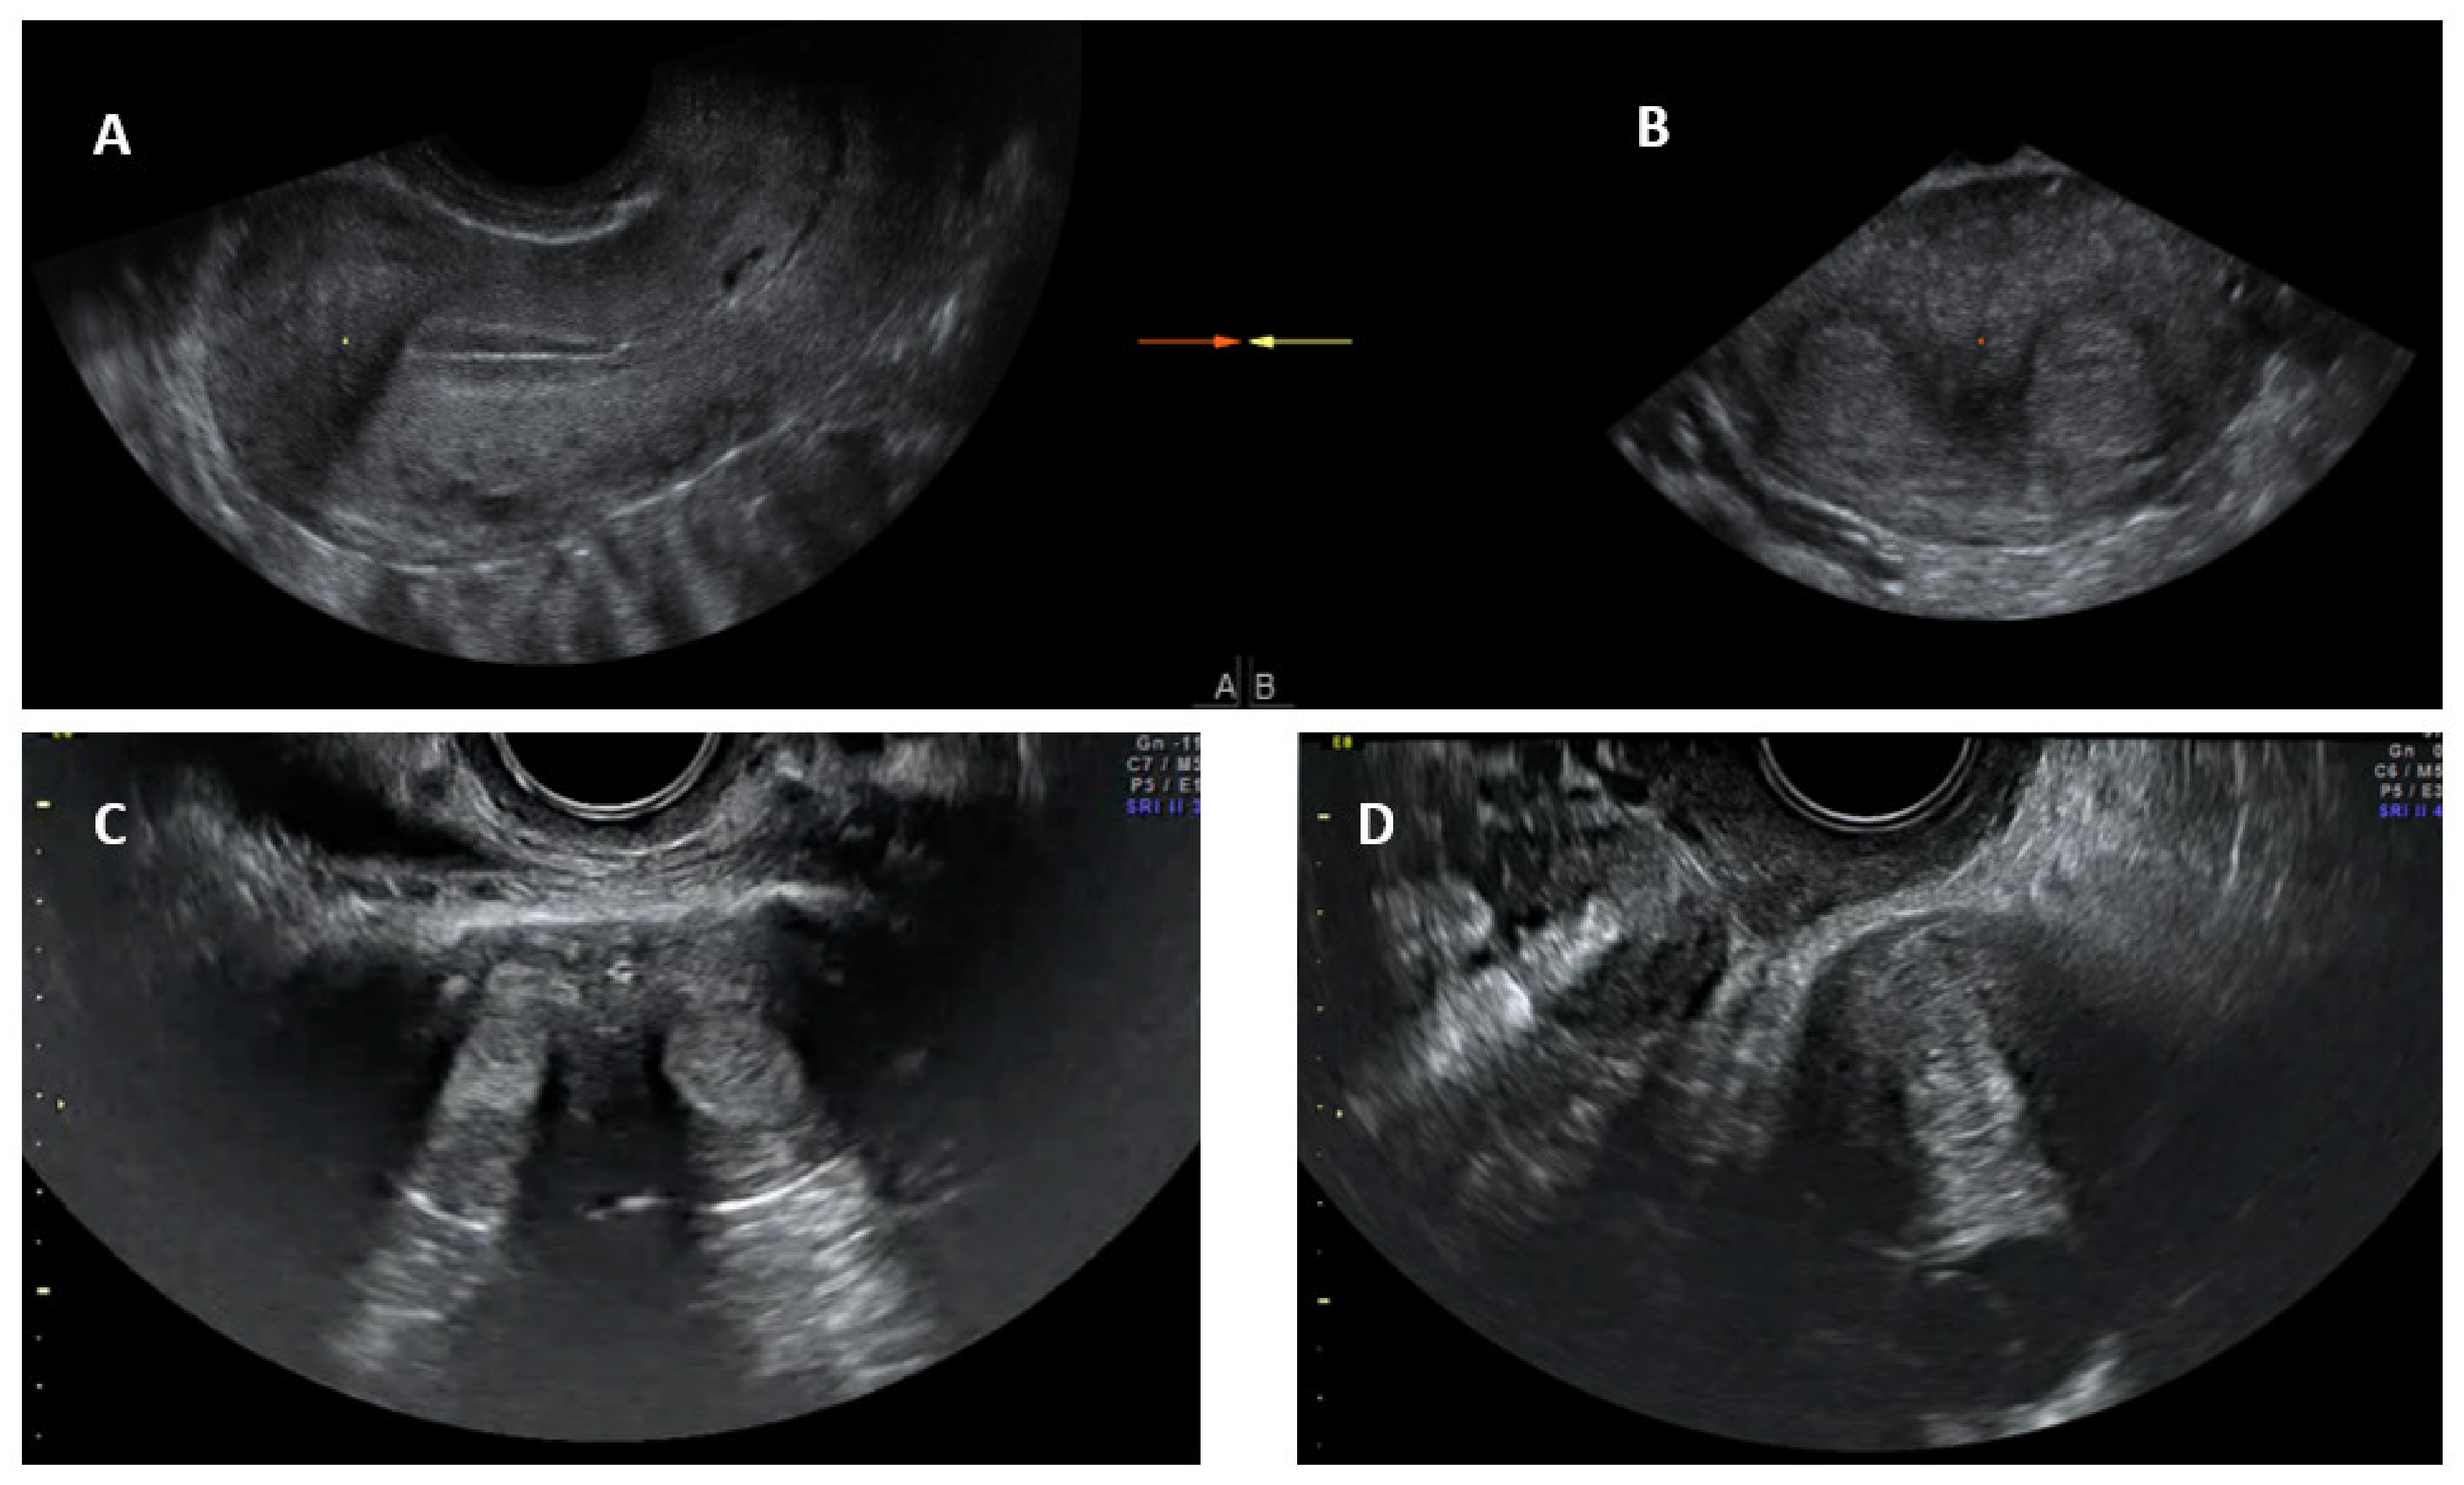

Conventional transvaginal ultrasound is minimally invasive and a less expensive way of assessing uterine morphology and ruling out uterine anomalies [13]. Ultrasound evaluation can be timed in the secretory (luteal) phase of the menstrual cycle as the endometrium, being bright and echogenic, is easy to visualise; ultrasound is therefore more appropriate for evaluating the uterus for congenital anomalies. The visualisation of a double endometrial complex on a transverse plane points towards a uterine anomaly (Figure 4) and the differential diagnosis would be a bicornuate, septate, subseptate or arcuate uterus. However, 3D ultrasound facilitates simultaneous visualization of both the external (serosal surface) and internal (endometrial) contours of the uterine fundus through its unique feature of providing the coronal plane of the uterus and can correctly classify the uterine anomaly into a bicornuate, septate or subseptate, or arcuate uterus [14].

Systematic scanning through the longitudinal plane of the uterus may reveal a uterine complex that then disappears while moving to the opposite side, followed by the appearance of a second uterine complex, suggesting that the uterus may be a partial or complete bicorporeal uterus (bicornuate or didelphys). The transverse plane provides more information and widely placed double endometrial echoes, especially at the upper portion of the uterus towards the fundus (Figure 4C), and an indentation at the fundus on an oblique plane (if obtainable) are typical of a bicornuate uterus. The double endometrial echoes will be closer in a septate uterus (Figure 4B) in contrast to that in a bicornuate uterus. The distance between the serosal surface and the upper border of the endometrial echo in a longitudinal plane may also give a clue to distinguish between septate and bicornuate uterus, although not confirmatory. In uterus didelphys, the two whole uterine body with endometrial echoes will be separate to each other and placed apart (Figure 4D), and the clinical demonstration of two cervices confirm the diagnosis. Two uterine horns may be symmetrical or asymmetrical and two separate vaginas may be seen on speculum examination.

Figure 4. Longitudinal section of subseptate uterus in midsagittal plane (A); transverse plane of a subseptate uterus showing two endometrial echoes (B); transverse plane of a bicornuate uterus showing two endometrial echoes (C); transverse plane of uterus didelphys showing two uterine bodies (D).